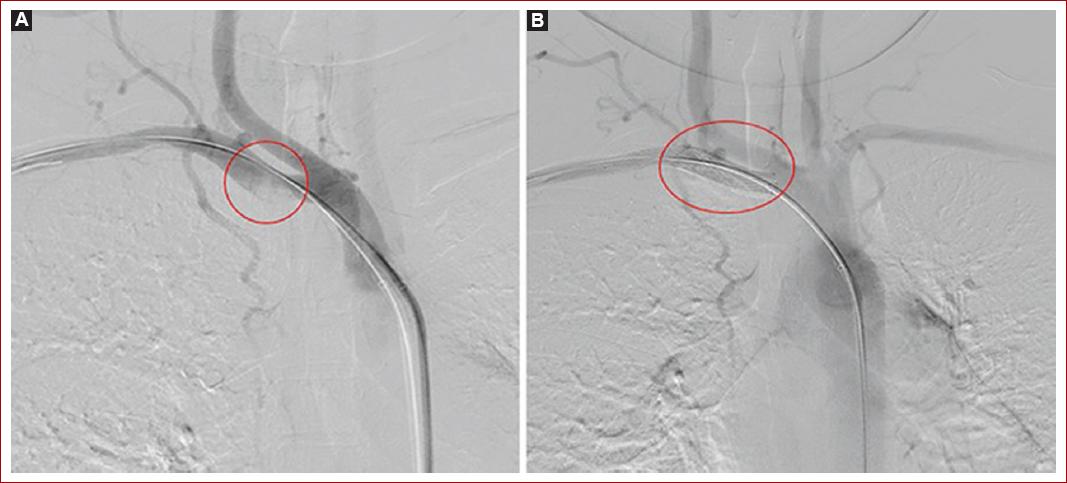

Durante la estancia en unidad de cuidado intermedio se evidencia progresión de cianosis y frialdad de la extremidad, con llenado capilar mayor a 5 segundos, por esto es revalorada por cirugía vascular, confirmando progresión de la lesión, con aparición de zonas de necrosis en regiones subungueales, razón por la cual se realiza de urgencia arteriografía periférica + trombectomía (Figs. 1B y 1C). Durante el procedimiento quirúrgico se evidencia a nivel de la primera porción de la arteria subclavia presencia de lesión trombótica oclusiva del 70% con alto riesgo embolígeno (Fig. 2A), por lo que se procede a realizar trombectomía con sistema Solent de Angiojet. Sin embargo persiste con estenosis residual de más del 30% por un coágulo crónico, por lo que se decide fijar con un stent de nitinol 8 x 60 para disminuir el riesgo embólico (Fig. 2B). Igualmente, a nivel distal de la arteria braquial se evidencia oclusión del 90% con ausencia de flujo a arteria cubital, radial e interóseas (Fig. 3A), por lo que se realiza trombectomía más paso de balón de angioplastia de 3A a largo de la arteria radial, logrando recanalización completa (Fig. 3B).

Figura 2 Arteriografía periférica de arteria subclavia derecha + trombectomía. A: imagen de trombo agudo en la primera porción de la arteria subclavia derecha con estenosis de más del 70%. B: recanalización completa de la lesión con stent de nitinol 8 x 60 respetando la salida de la arteria carótida.